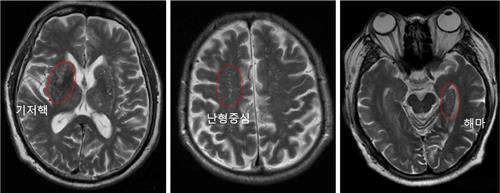

알츠하이머는 치매 중 가장 흔한 유형으로, 전체의 약 60∼80%를 차지한다. 나이가 들수록 발병 위험이 커지며, 노인성 치매의 대표적인 원인 질환이다. 알츠하이머병 진단을 위한 뇌 영상 검사에서 흔히 발견되는 뇌혈관 주위 공간 확장은 뇌의 노폐물과 독소를 청소하는 기능에 문제가 생겼다는 것을 의미한다.

연구팀은 알츠하이머병 진단 환자들에 대한 뇌 자기공명영상(MRI) 검사를 추가로 시행해 뇌혈관 주위 공간 확장의 정도에 따른 인지기능 점수를 평가했다.

이 결과 뇌혈관 주위 공간 확장 정도가 심한 환자군은 그렇지 않은 환자군보다 매년 인지기능 점수가 0.58점씩 빠르게 감소하는 것으로 분석됐다.